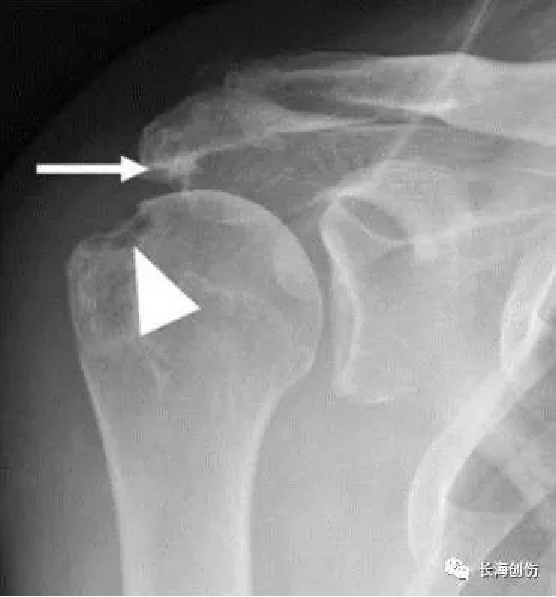

X线检查:一般无阳性改变,存在肩袖损伤的间接征象:可表现为肱骨大结节囊性变、肩峰下前1/3骨质硬化、肩锁关节退行性变和肱骨头上移。